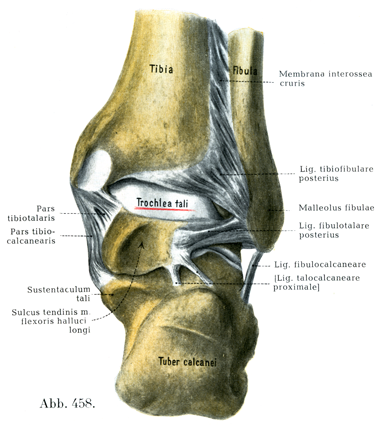

[図458] 右の足関節 後からみる(4/5) 関節包はとり去ってある.

特別の装置として6つの側副靱帯があへそのうち3つが脛骨踝から,他の3つが腓骨踝から起る.脛骨からの3つの靱帯は密に相接して三角靱帯Lig. deltoidesとよばれる三角板を形成する.

三角靱帯の脛舟部Pars tibionavicularisは幅およそ5mmで,脛骨踝の前縁と先端から起って,舟状骨の上面と内側面につく(図459, 463)

三角靱帯の脛踵部Pars tibiocalcanearisは幅およそ1cmで,はなはだ丈夫である.脛骨踝の外面から起って踵骨の載距突起につく.その最前部の線維束は踵舟靱帯に移行している(図457, 459)

三角靱帯の脛距部Pars tibiotalarisはFickによれば幅およそ15mm,厚さ約5mmである.後脛骨筋の腱鞘によって被われ,脛骨踝の下縁から起って斜め下方に走り,距骨滑車の脛側踝面の縁につく(図458, 459)

前距腓靱帯Lig. fibulotalare anteriusは腓骨踝の前縁から起り,距骨滑車の腓側踝面の前縁につく.幅は約1cmで,あまり丈夫なものではない(図460, 463).

踵腓靱帯Lig. fibulocalcaneareは腓骨踝の前縁の下部から起り(先端からは起らない),斜め後下方に走って踵骨の外側面につく.幅8mm,厚さ5mm,長さ2cmほどである(Fick).この靱帯の外側を長・短腓骨筋の腱が走っている(図457, 458, 460, 463)

後距腓靱帯Lig. fibulotalare posteriusはほぼ水平に走る.腓骨踝窩から起り,距骨の近位突起につく.この靱帯は3つの外側の靱帯のうちで最もつよい(図458).